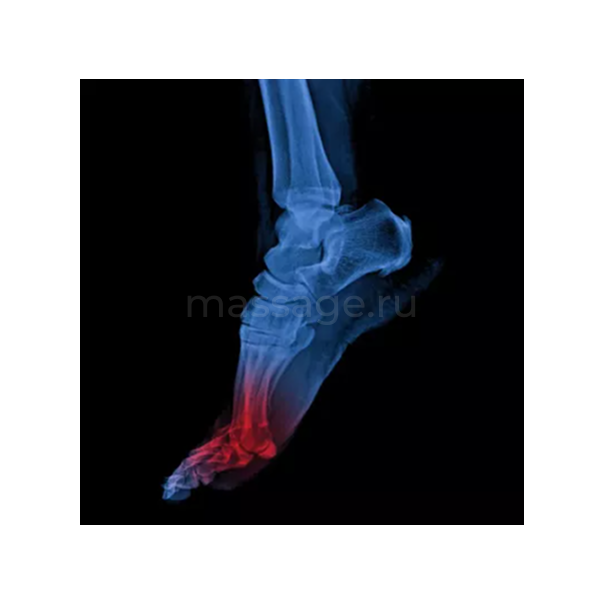

Еще одна важная причина нарушения функции ПФС большого пальца – гиперпронация стопы. Сама пронация – естественное и необходимое движение стопы, включающее эверсию (пронацию), абдукцию и тыльное сгибание (дорсифлексию) в подтаранном суставе. Однако избыточная пронация может иметь серьезные биомеханические последствия для большого пальца и всего тела. Первый визуальный признак избыточной пронации – плоскостопие, а именно опущение медиального продольного свода (Изображение 10).

Не стоит забывать и о другом проявлении гиперпронации – отведении стопы наружу (Изображение 11). В

результате при переносе веса тела через стопу во время шага нагрузка распределяется не равномерно по всем пальцам, а чрезмерно концентрируется на большом пальце. Причем из-за специфического угла приложения силы большой палец отклоняется наружу (латерально) – возникает вальгусная деформация (hallux valgus), сопровождающаяся характерной «косточкой» (бурситом). Все это увеличивает механическую нагрузку на ПФС большого пальца, нарушает его функцию и со временем приводит к ограничению разгибания. Причины гиперпронации многочисленны и выходят за рамки этой статьи. Важно, что массажисту следует работать не только с непосредственной гипомобильностью ПФС, но и с ее первопричинами.